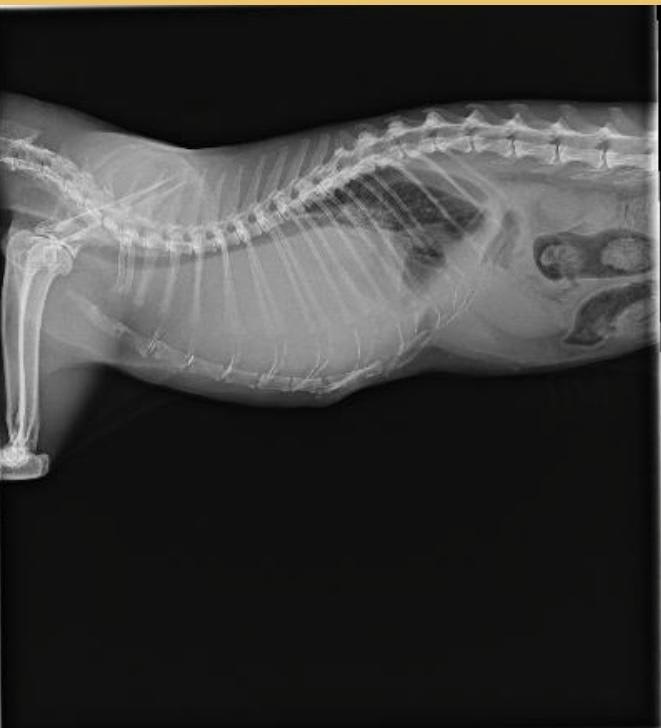

We just put our almost 14 year Siamese girl to sleep last week. Seizures started around age 12. Vet suspected brain tumor due to her age & not epilepsy. For the past eight month there was a slight cough, muscle loss, hind end weakness, and sometimes a little wheezing sound also put on kidney diet. Brought into vet because she began to take on a strange odor and was starting to gasp for air. Here is xray. We assumed fluid, but chest tap got only little blood out of various spots. Thoughts?

Hi, thanks for using Petco Pet Education Center, formerly Petcoach! I am so sorry for your loss! I do see pleural effusion (fluid) on the X-ray but I would also suspect a mass, which is likely the cause of the fluid. That could be why your Vet couldn't get any. Most of the white on the X-ray is likely the mass and only a small amount of fluid. I wish you the best!